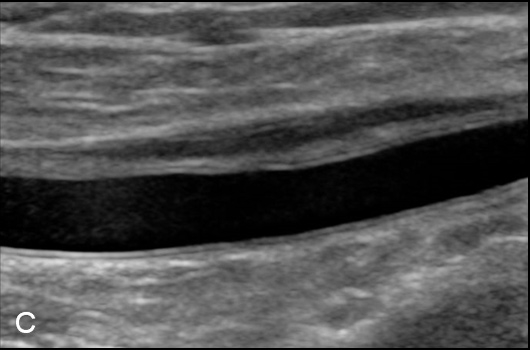

Figure 3

Duplex Sonographic (DS) images from three distinct arterial segments. Arterial segment (A) is classified as “vasculitis”, with homogenous, hypoechoic wall broadening, segment (B) as “arteriosclerosis”, with eccentric, irregular plaques and acoustic shadowing, and segment (C) as “normal”, showing a thin homogenous intima/media layer.